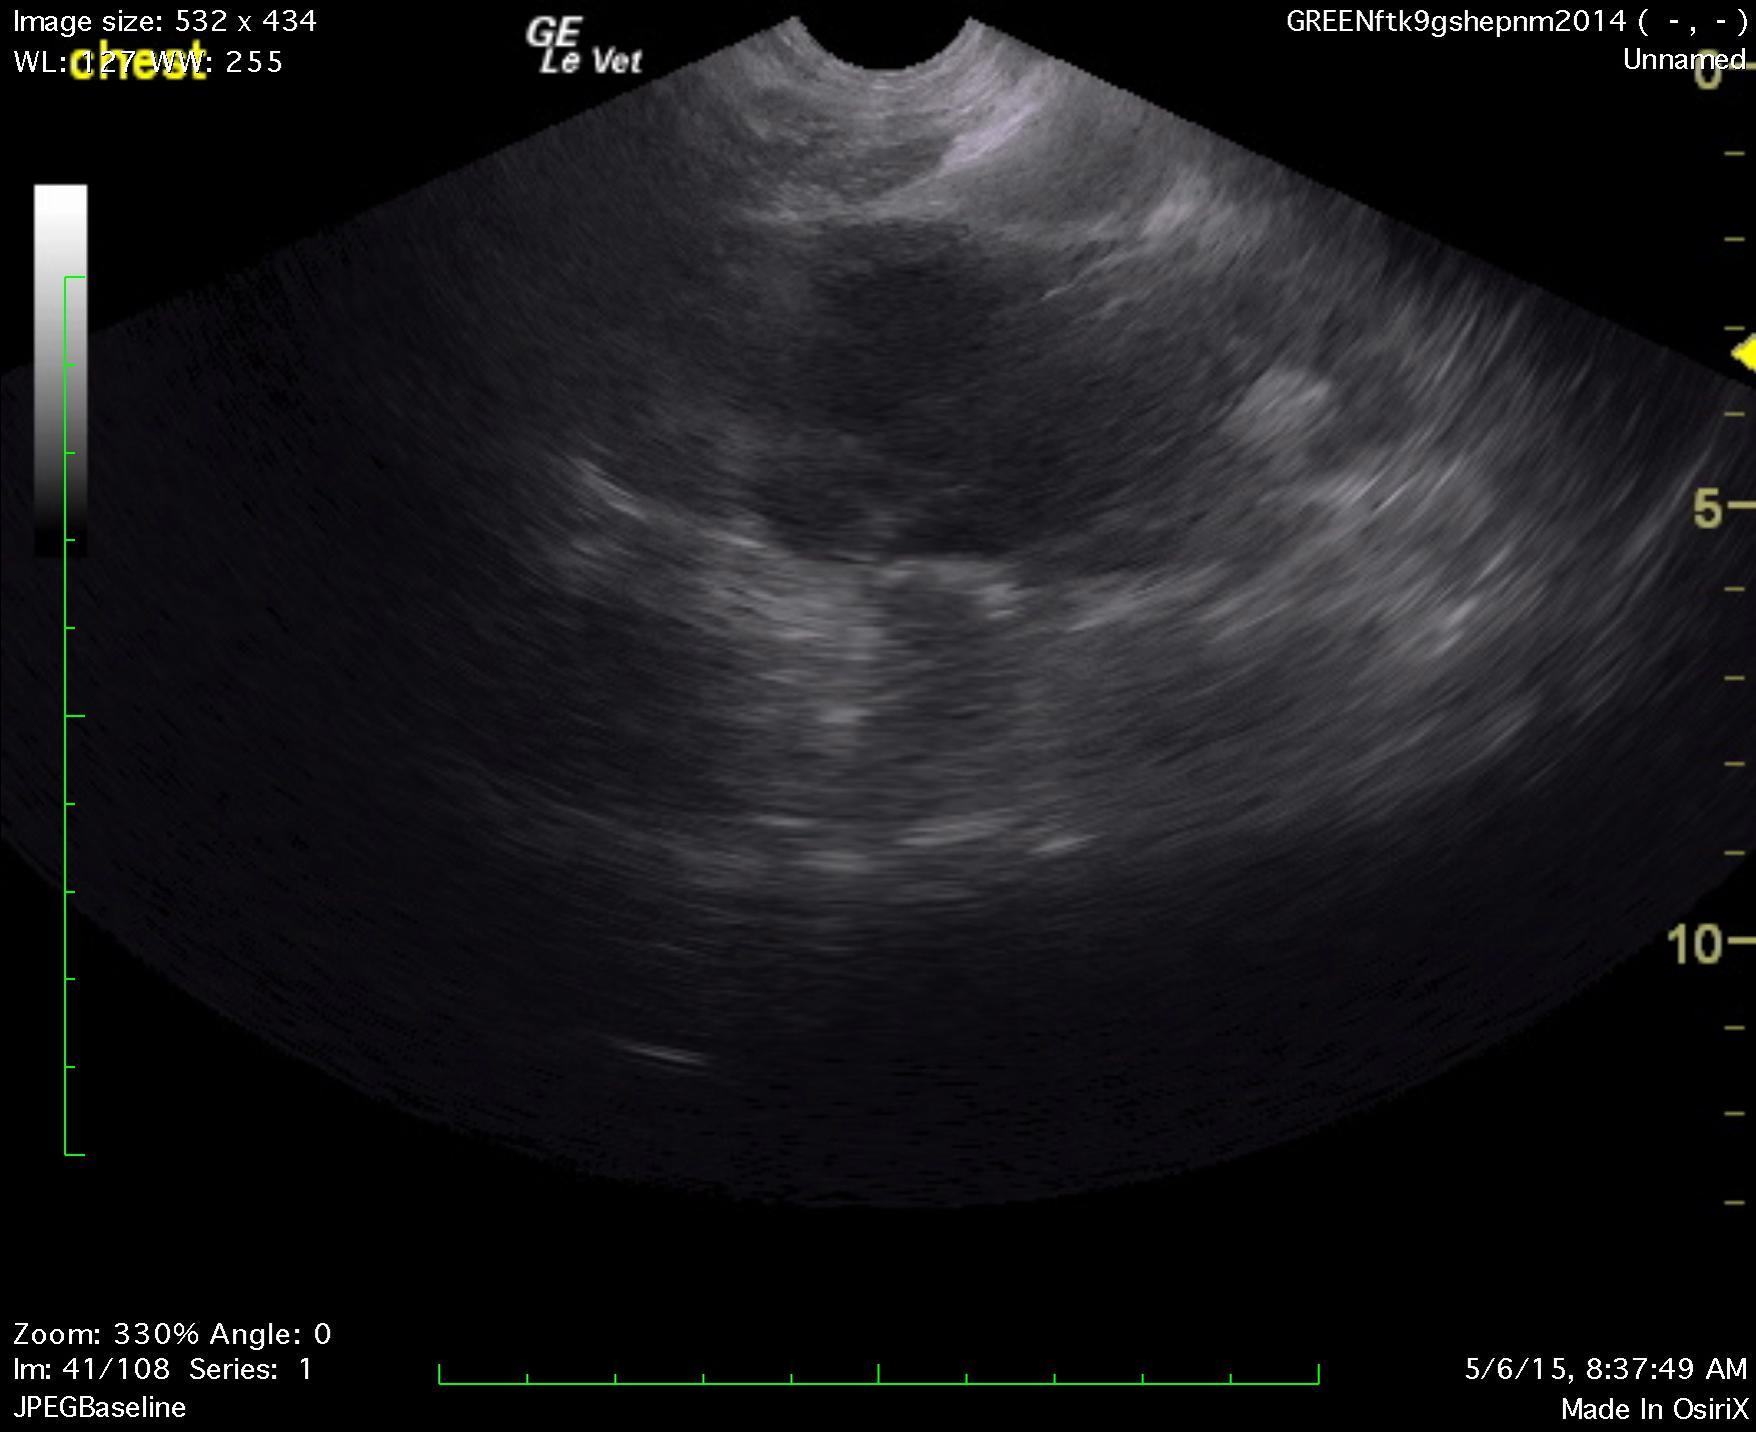

A 1-year-old NM German shepherd with a history of PU/PD and hypercalcemia was presented for evaluation of lethargy, weight loss, and anorexia. Left-sided nephromegaly was present on survey radiographs. Abnormalities on serum biochemistry were hypercalcemia, azotemia, and mildly elevated ALT activity.